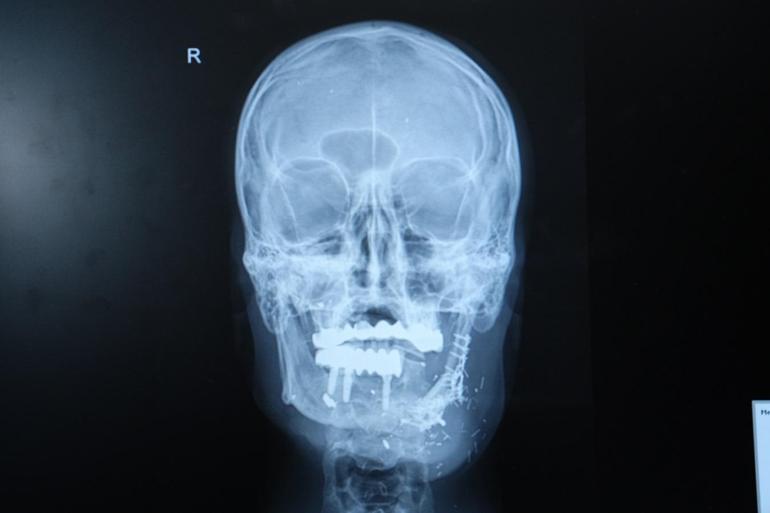

Hastanın durumunun oldukça komplike olduğunu dile getiren Doç. Dr. Özkan, “Hastamız ateşli silah yaralanması sonrası çenesinin yarısını kaybetmişti. Daha önce farklı merkezlerde ameliyat olmuş fakat nakiller başarısız olmuştu. Hem çene bütünlüğünü sağlamak hem de ileride implant yapılabilecek sağlam bir kemik dokusu oluşturmak gerekiyordu. Hastanın bacağından aldığımız kemiği mikrocerrahi yöntemle çeneye naklettik. Damarlara bağlantı yaptık, plaklarla sabitledik. Bu sayede hem fonksiyonel hem de estetik olarak başarılı bir sonuç elde ettik” dedi.

Doç. Dr. Özkan, bu tür vakalarda mikrocerrahinin önemine dikkat çekerek, “Kompozit doku eksikliklerinde vaskülerkemik transferi bize büyük avantaj sağlıyor. Hastamız şu an kendi beslenmesini sağlayabiliyor. Önümüzdeki süreçte kemik iyileşmesini tamamladıktan sonra diş implantları yerleştireceğiz ve hastamız çok daha rahat beslenebilecek” ifadelerini kullandı.